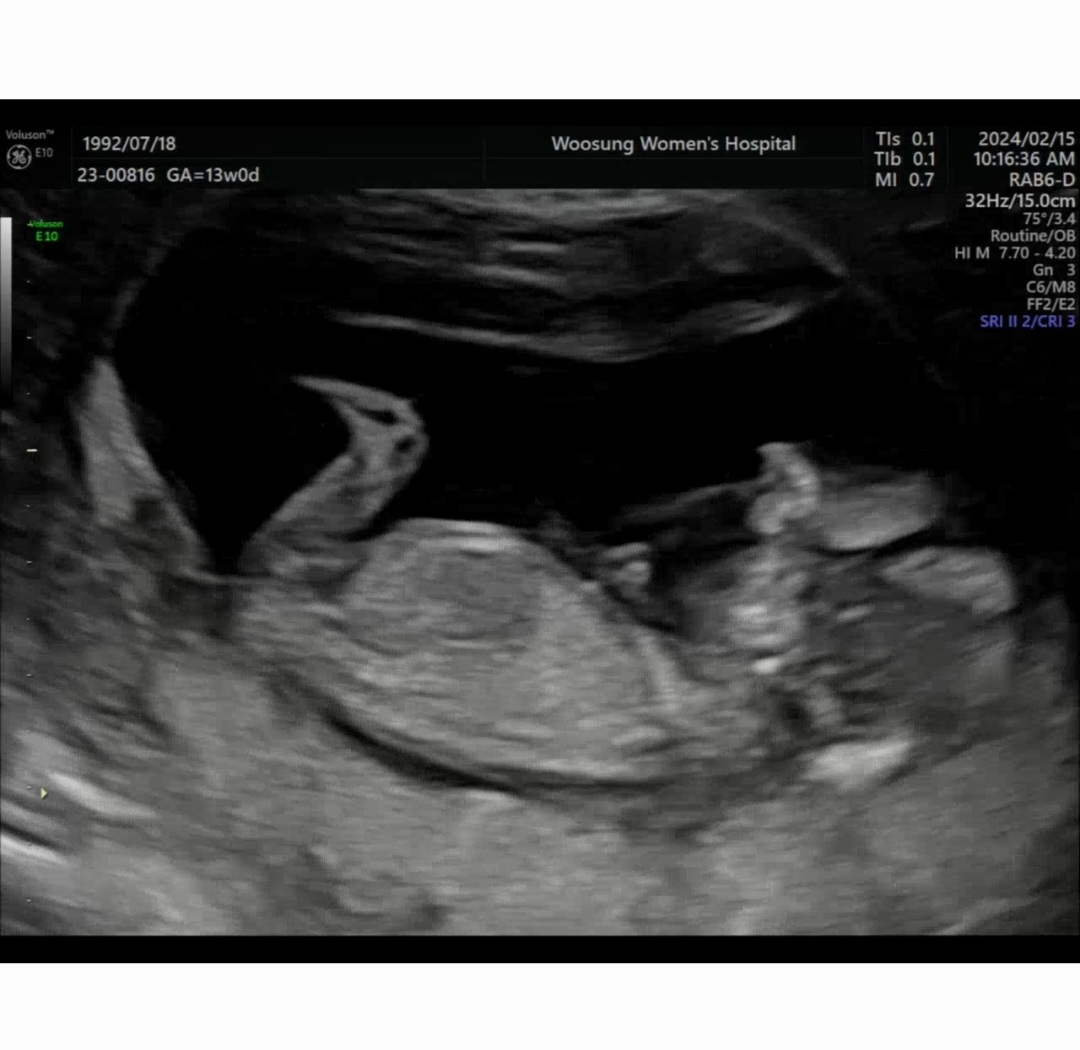

13주 딸이겠죠???🍑 힌트좀주세요ㅠㅋ

땡기는 음식이며 태몽 다 딸을 가리키고 있는데 13주차 사진으로 성별 알수있을까요? 다리에 가려져서 아직 모를까요 ㅠㅠ